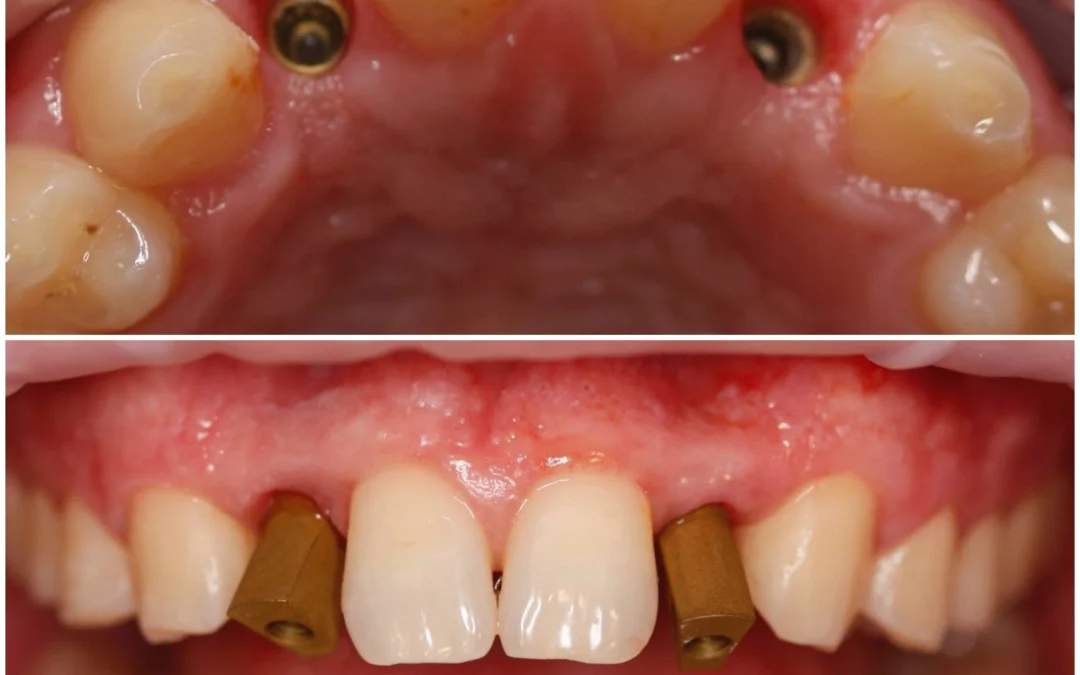

Ренат Ризванов | Клинический кейс RR-40

Небольшой рекол в 1 год после имплантации в область адентии двоек на верхней челюсти. - Имплантация MIS C1 узкая платформа. - Connect абатменты. #mis #misC1 #connect...